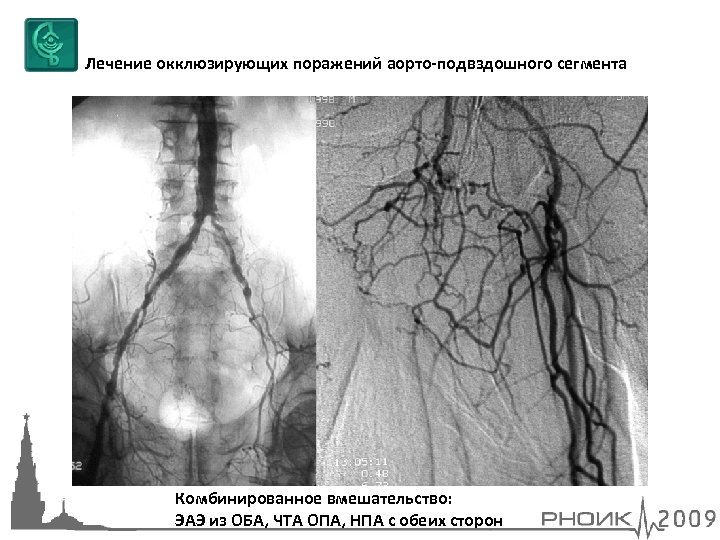

Лечение окклюзирующих поражений аорто-подвздошного сегмента Комбинированное вмешательство: ЭАЭ из ОБА, ЧТА ОПА, НПА с обеих сторон